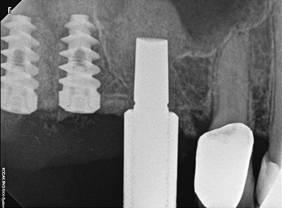

Danach werden dort Implantate eingesetzt.

Beachten Sie bitte, dass alle Implantate mit

dem Knochenersatzmaterial komplett bedeckt sind.